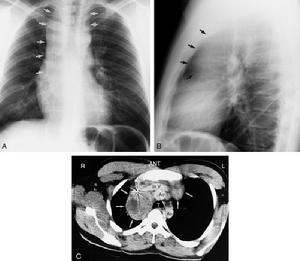

霍奇金病確診後應進一步進行分期,由於不少患者經一般檢查僅有一組頸淋巴結腫大,診斷為I期,但常已有縱隔或腹腔轉移,故僅靠臨床檢查約有1/3病人分期不準確,故應做下列檢查。

(1)胸部及縱隔X線斷層攝片:可發現肺門淋巴結腫大和肺部浸潤。

(2)下腔靜脈造影和靜脈腎盂造影:前者可發現第二腰椎以上主動脈旁腫大的淋巴結,後者可顯示輸尿管是否移位,此外做腹部放療時需了解腎臟位置。

(3)雙足淋巴管造影(pedallymphogram):可早期發現腹腔和主動脈旁淋巴結腫大。

(4)骨骼X線片以了解有無骨骼被侵犯。